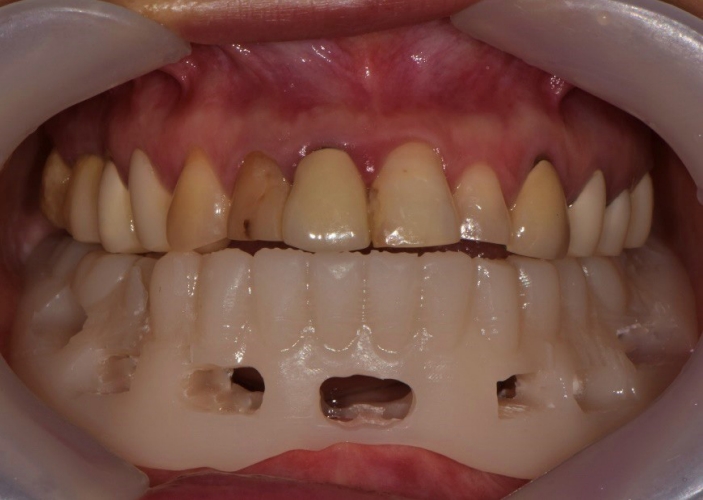

Fig. 11.

Immediate provisional restoration with 3-dimensional prinited denture is placed.